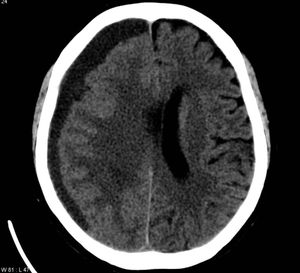

A 73-year-old man who is a chronic alcoholic is brought to the Emergency Department by an ambulance. He was found collapsed in the street. On admission his airway, breathing and circulation are satisfactory. His GCS is 13/15 (eyes = 3, verbal = 4, movement = 6) although his level of consciousness appears to be fluctuating. There are no obvious signs of external head injury. A CT head (without contrast) is performed: What is the most likely diagnosis? A-Subarachnoid haemorrhage B-Wernicke's encephalopathy C-Subdural haematoma D-Meningioma E-Extradural haematoma

not sub arachanoid hemorhage becuase it does not create a space occupying image not meningioma becuase of no edema in the picture and no mass sub dural fits because of the concave border, epidural will have convex

yup, its great thing to exclude answers before giving the right one, this shows that you know all about other options, this is also a chronic SDH